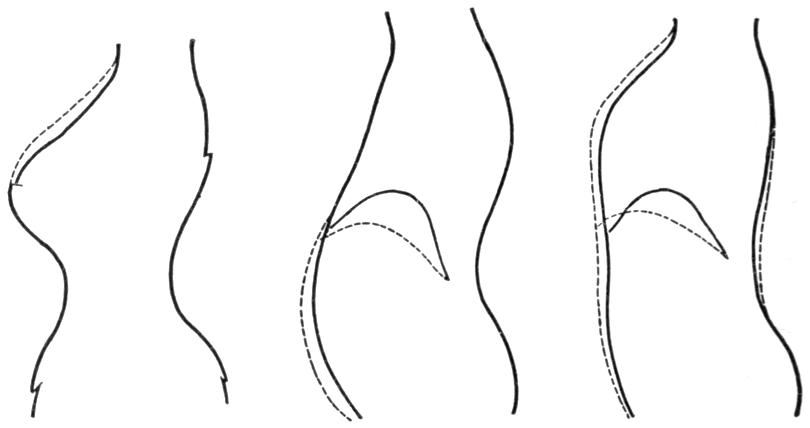

| III. | The Skeleton | H 28 |

| IV. | The Muscles | H 39 |